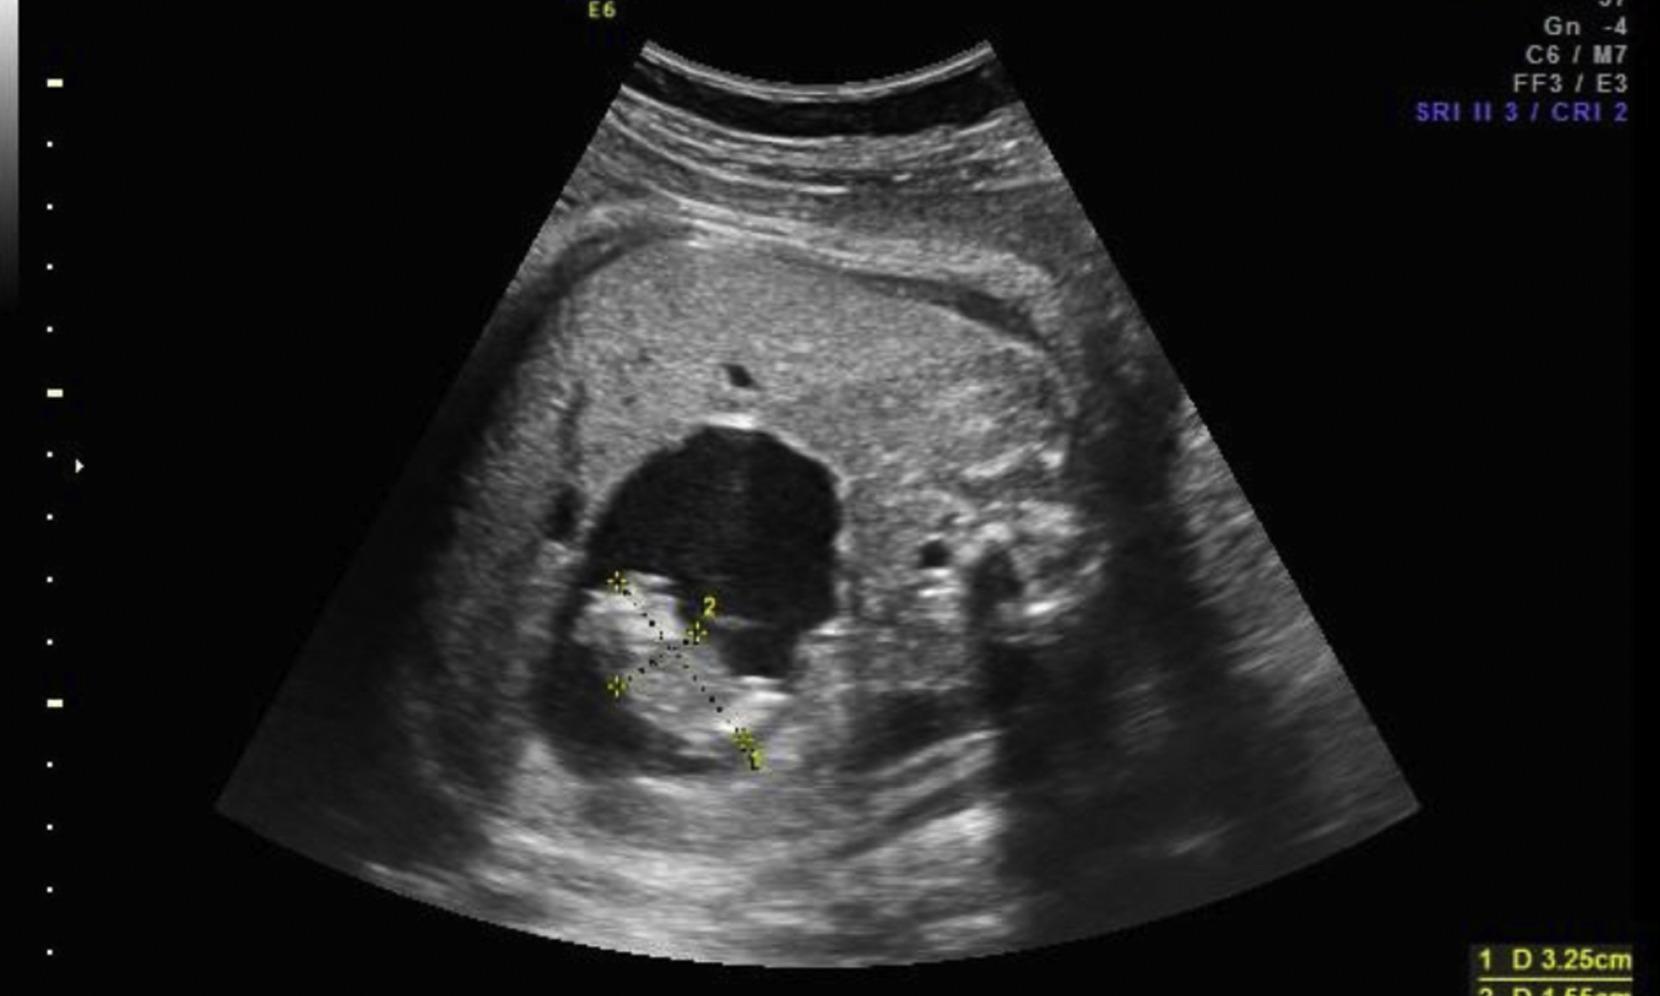

Initial examinations revealed abnormal growth inside her abdominal cavity, it said, adding that further imaging confirmed that the child was carrying two malformed babies within her abdominal cavity.

"This rare condition happens early in pregnancy, when one baby surrounds and traps another inside its body. The trapped baby cannot grow or survive. In this baby's case, both malformed babies were enclosed within a single sac, making it an exceptional medical rarity," the statement added.